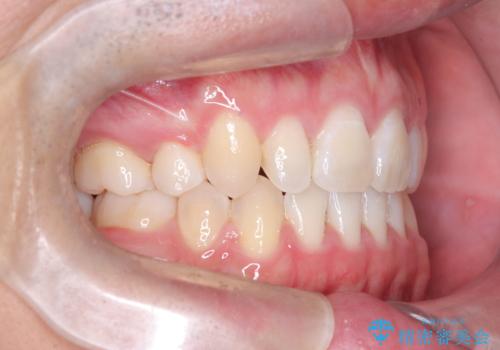

正中の改善と前歯の整列:抜歯を伴う矯正治療の症例

- 前歯のガタガタや正中の不整を改善するために、右上4、左上4、左下4を抜歯し、矯正治療を行いました。この治療により、見た目だけでなく、咬合のバランスも改善され、患者様の口腔内の健康が向上しました。